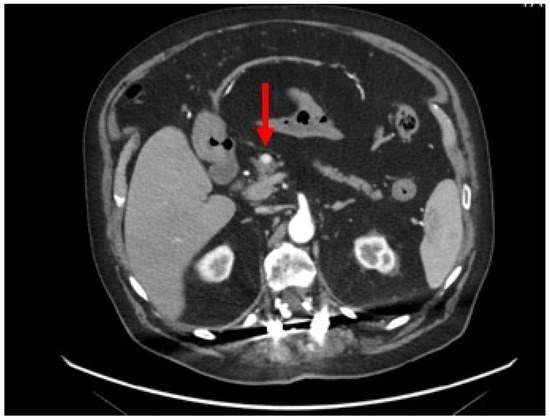

2. Case-Report